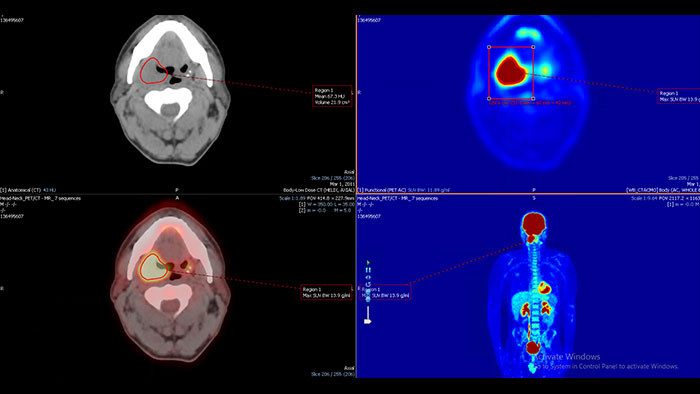

Streamlined workflow for follow up and analysis of oncology patients

MMTT is a post processing software used to display, process, analyze and quantify anatomical and functional images, for CT, MR, PET/CT, SPECT/CT and Dual Energy CT at one or multiple time points.